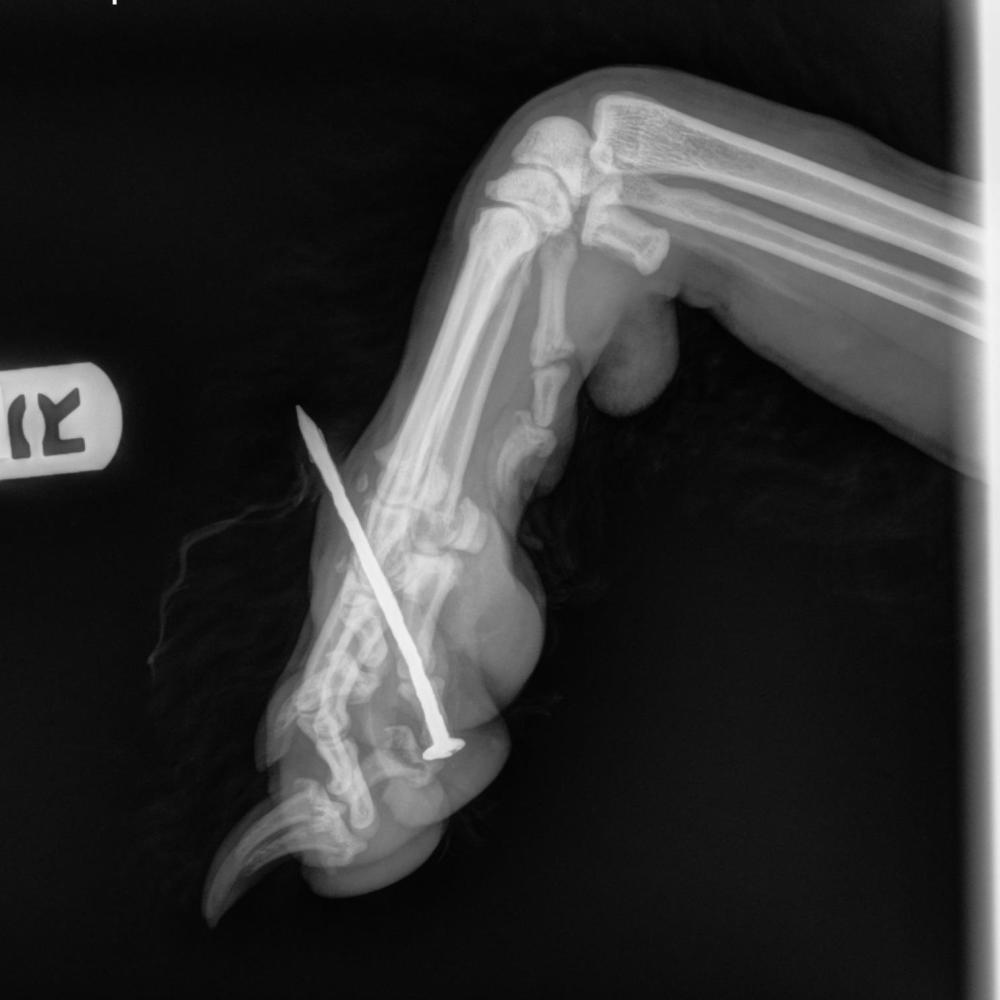

A Real Example: Bowie’s Snow Day Surprise

Bowie, a playful goldendoodle, was playing in the snow when his family noticed him limping and brought him to DoveLewis for help. Turns out, Bowie had stepped on a hidden nail beneath the snow. Our team removed the nail, cleaned and treated the wound, and started him on pain medication and antibiotics. Thanks to his family's quick response, Bowie recovered fully and was back to enjoying snowy outings—this time with a little extra caution.